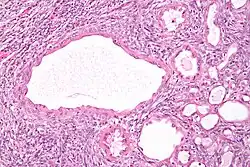

| Micrograph of a cystic nephroma (left of image). Normal kidney is seen on the right. H&E stain. | |

The characteristics of cystic nephromas are:

- Cysts lined by a simple epithelium with a hobnail morphology, i.e. the nuclei of the cyst lining epithelium bulges into the lumen of the cysts,

- Ovarian-like stroma that has a:

- Spindle cell morphology, and has a

- Basophilic cytoplasm.

Micrograph of a cystic nephroma. H&E stain.